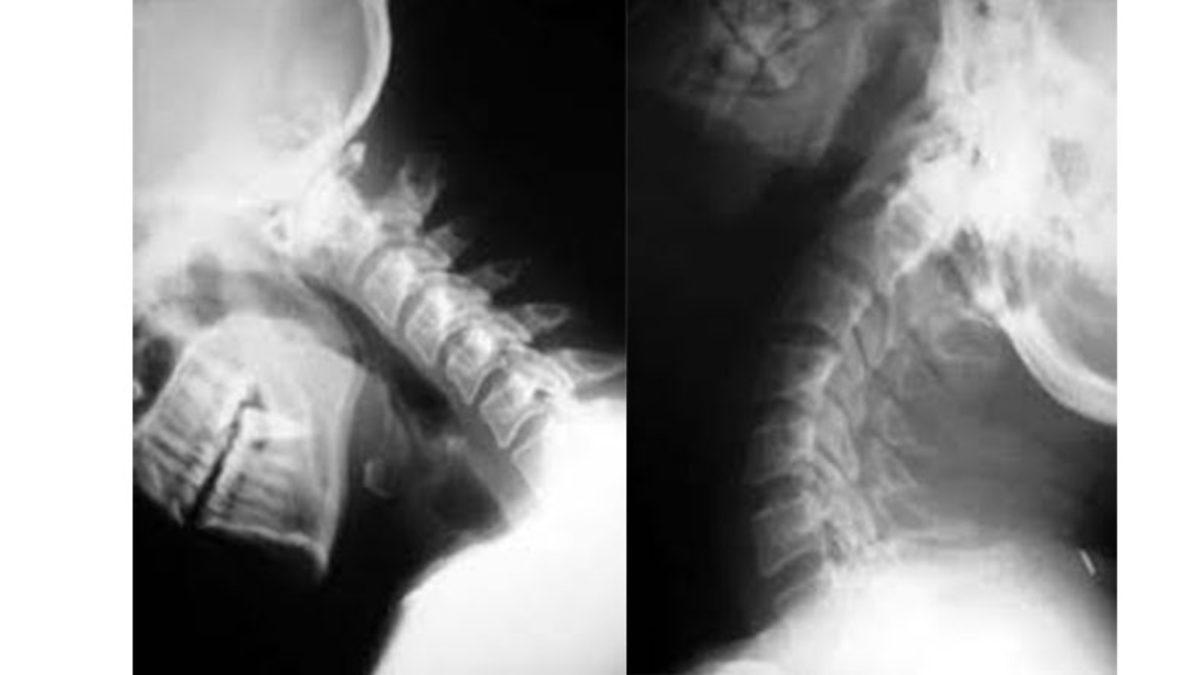

İç dekapitasyon (internal decapitation), tıp literatüründe kraniyoservikal disosiyasyon olarak da biliniyor.

Kafa kemiği ile boyun omurlarını bir arada tutan bağ dokularının yırtılması veya kopması sonucu ortaya çıkan bu durumda, kafa fiziksel olarak vücuttan ayrılmıyor. Daha da kötü bir durum yaşanıyor: Kafa ve boyun arasındaki stabilite bozuluyor.

Fakat içeride, kafa ve boyun arasındaki bağlar ciddi şekilde zarar gördüğü için, boynun vücutla bağlantısı zayıflar ve omurilik gibi hayati sinir dokuları zarar görebilir. Omurilik ve beyin sapı gibi vücudumuzu kontrol eden yapılar zarar gördüğü için hayatta kalma ihtimali de minimuma düşer.